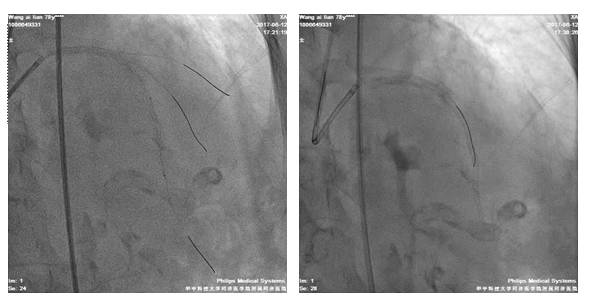

四日后,尝试左冠PCI术

股动脉路径

7F EBU3.5/GC

Runthrough NS,ASAHI SION,BMW导丝

2.5*20mm球囊扩张LAD10*12atm

先后与LAD远段-近段置入2.5*33mm、2.75*33mm、3.0*29mm DES支架,三支架串联